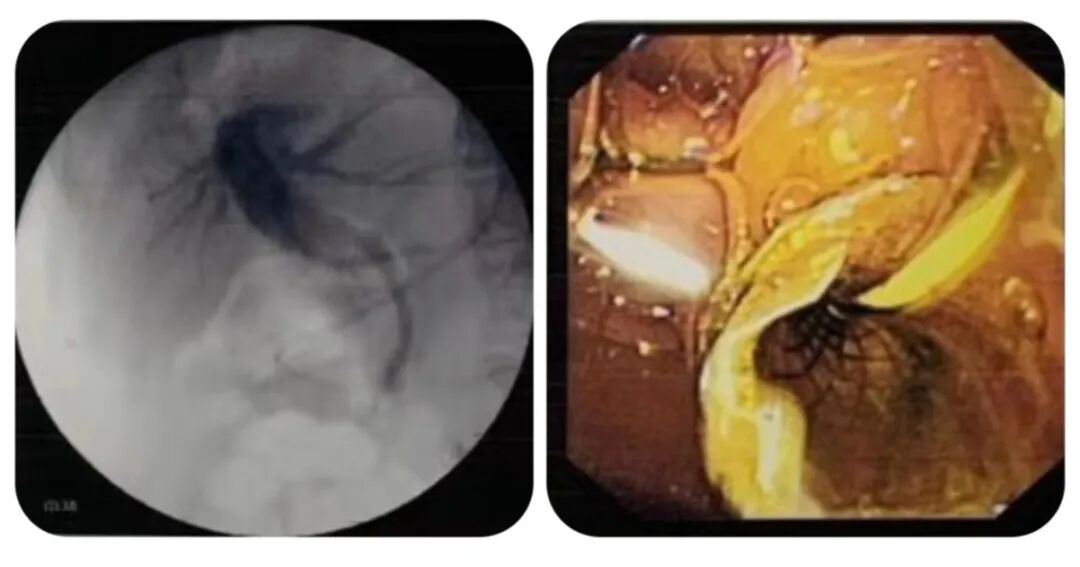

2、对于已经出现胆管受压引起的梗阻性黄疸,消化内镜医生可以通过ERCP下胆管支架置入或超声胃镜引导下胆道穿刺引流(EUS-BD)解除胆道梗阻。

ERCP下置入胆道金属覆膜支架

晚期胰腺癌虽然预后差、生存率低下,但我们仍可以通过积极有效的治疗在一定程度上延长患者的生存期,改善终末期患者的生存质量。文首的卢老爷子在我们这里先通过EUS-FNA获取病理得到了确诊,紧接着就在ERCP下置入胆道金属支架,黄疸指数从三百多迅速降至八十多,再同时辅以保肝胰酶等治疗,半月后老爷子就顺利出院了。

3、超声胃镜引导下胆道穿刺引流(EUS-BD)、ERCP下胆管支架置入术打通胆道,迅速解除黄疸,内镜下胃肠道支架置入解除胃肠道梗阻,提高晚期胰腺癌患者的生活质量,延长患者的生存期。

ERCP团队进行胆道支架置入